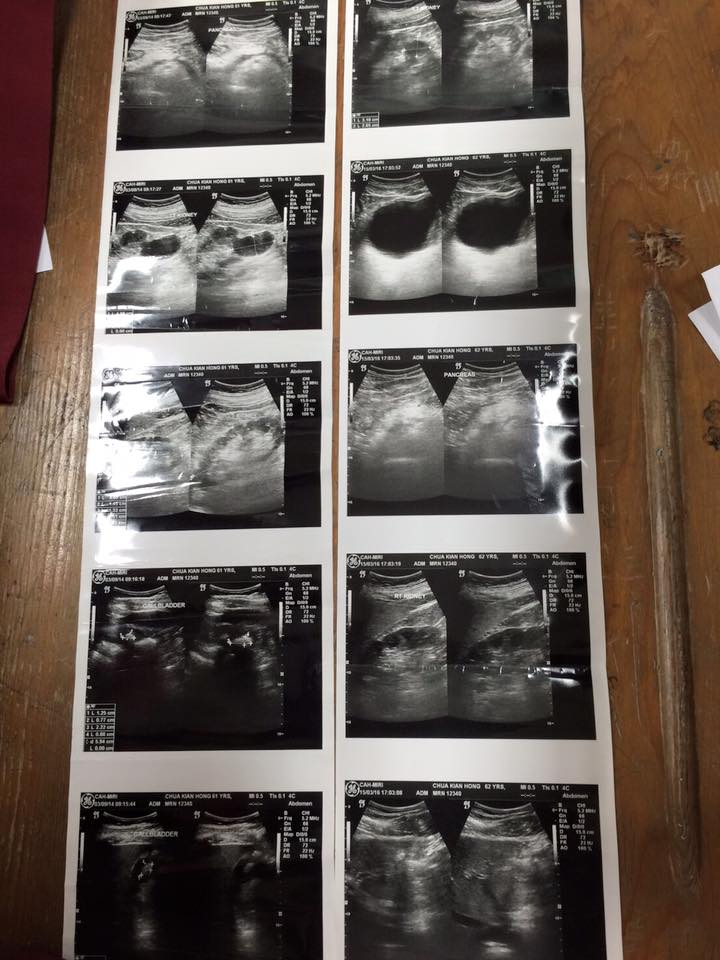

感應連連~蓮生活佛 盧勝彥法王加持弟子後奇蹟感應又一見證! 東馬美里萬法堂主席蔡健煌參加完2/28大幻化網法會後,原本被醫生診斷需要開刀的膽結石,竟奇蹟似的消失! 特地感謝師尊偉大的加持,不可思議! 附件:蔡健煌主席提供的醫院診斷證明。